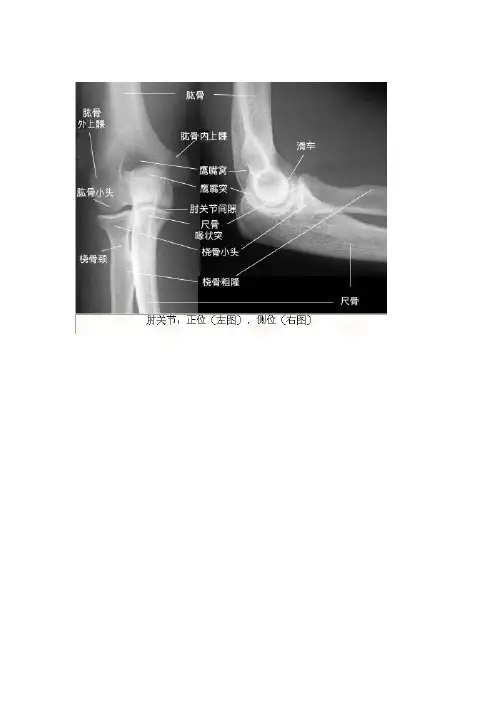

举报大叶性肺炎高血压心脏病消化道穿孔胸腔积液胸椎压缩性骨折右侧气胸右侧胸腔积液右肺炎右胫腓骨骨折右上肺炎右中叶肺炎正常胸片左侧胸腔积液左肱骨骨折风心病,梨型心胸部X线片系统读片原理24个字母(A-X)系统读片法,可以减少漏诊。